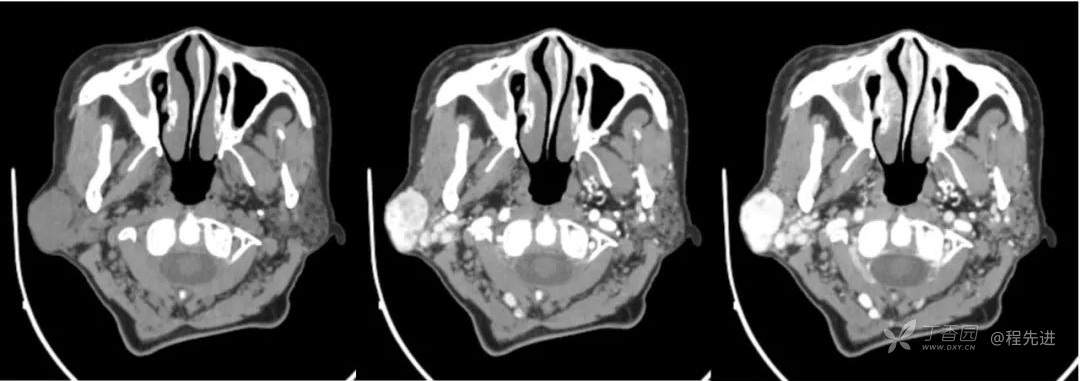

红五月特别精彩病例|发现右侧耳下肿物12年,罕见典型病例,见过就可以秒【病理公布】

简要病史:发现右侧耳下肿物12年,不痛,缓慢生长

既往史:19年前因右侧腮腺肿物在当地医院行手术(具体不详),17年前因右侧腮腺肿物复发再次在当地医院手术(具体不详)

体格检查:右侧耳下可扪及大小约3*3cm肿物,质地中,边界清,活动可,无明显压痛。颈部未扪及明显肿大淋巴结